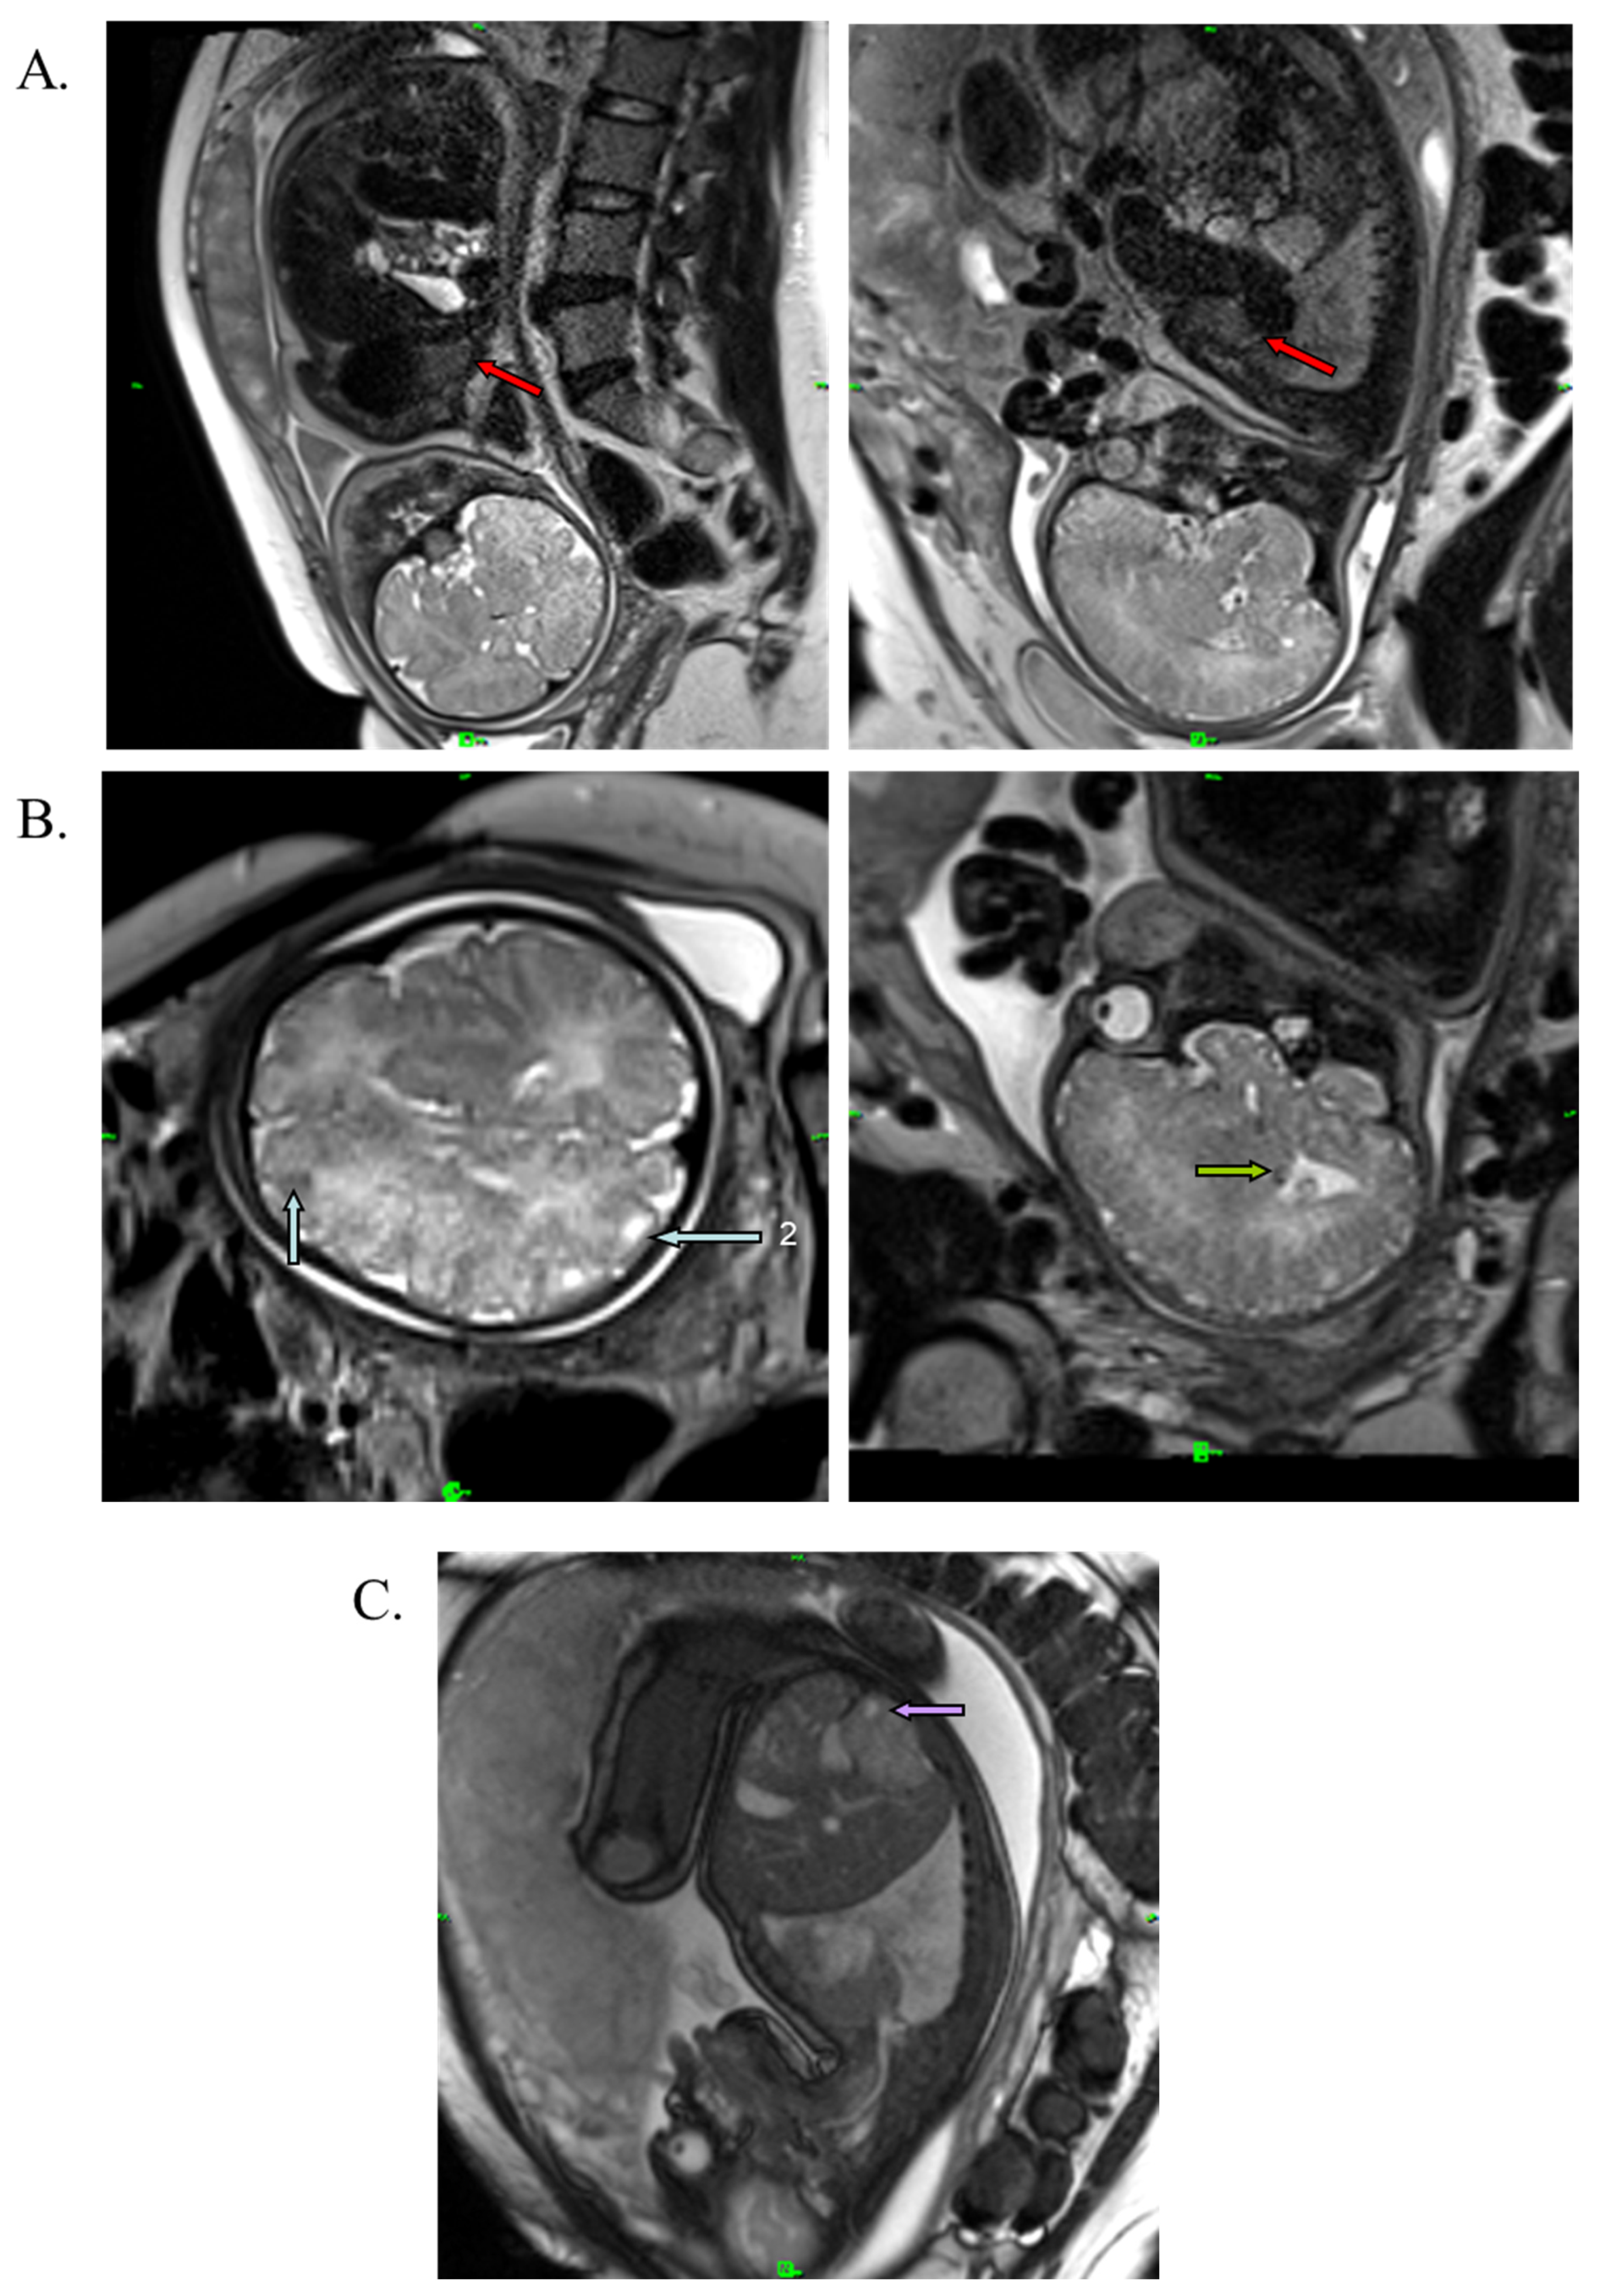

A medical team consisting of a cardiologist, clinical geneticist, obstetrician, and neonatologist decided to start oral immunosuppressant therapy for the mother (everolimus; Votubia). The goal of the treatment was to reduce the size of the rhabdomyoma, which lasted for five weeks. Oral everolimus was given daily. An initial dose of 10 mg/day everolimus was administered. The dose was adjusted to 5 mg/day from day 10 to set the 5–15 ng/mL target trough level (see Table S1). Blood values, including hemoglobin, leukocytes, leukocyte differentiation, thrombocytes, and CRP, were monitored during the treatment. All laboratory parameters were within the normal range. Everolimus reduced the size of the rhabdomyoma by almost half (20 × 20 × 33 mm) (Figure 3A). Everolimus was discontinued on day 36, two weeks before the scheduled cesarean section, to avoid complications and pre- and postnatal infection. The fetus and mother did not experience adverse events during the entire length of the treatment. Fetal MRI performed during the 38th week of gestation also revealed renal cysts in the fetus (Figure 3C).

Figure 3. T2-weighted MRI image of the fetus at the 38th week of gestation. (A) Red arrows show cardiac rhabdomyoma in reduced size (20 × 20 × 33 mm). (B) Blue arrows show cortical tuber in the gyral core (2), and green arrows represent subependymal nodule in the brain. (C) Purple arrow shows the renal cyst.